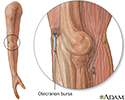

Bursa of the elbow - illustration

Bursa of the elbow

illustration